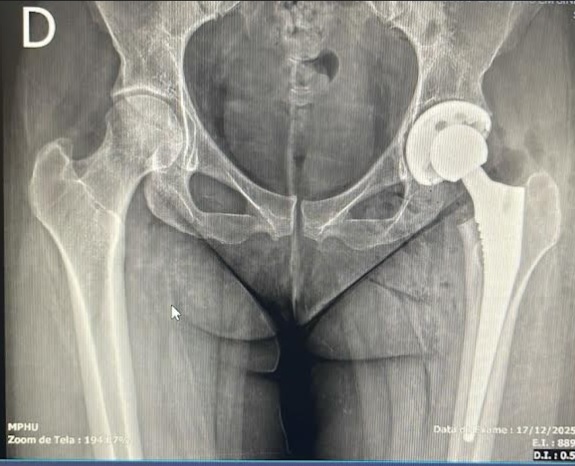

A cirurgia de prótese de quadril é um procedimento médico necessário em casos de artrose avançada, onde a dor intensa e a limitação de movimento comprometem a qualidade de vida dos pacientes. Compreender as dúvidas comuns relacionadas a este procedimento pode ajudar a desmistificar o processo e proporcionar segurança aos que estão prestes a enfrentá-lo.

Um fator que muitos pacientes consideram é a durabilidade da prótese. Em média, as próteses de quadril podem durar mais de 20 anos, dependendo do uso e da condição física do paciente. Essa longevidade faz da cirurgia uma opção viável para aqueles que buscam melhorar a qualidade de vida por um longo prazo.